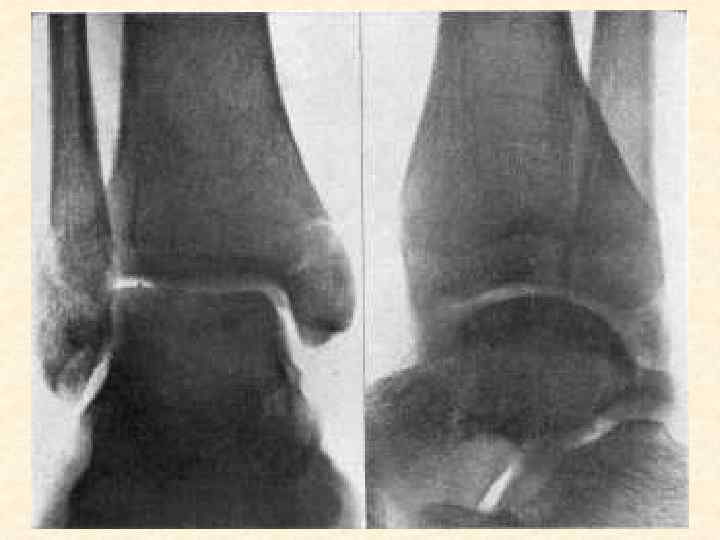

Заболевания, поражающие костную систему • • • Остеомиелит, артрит Артроз Остеопороз Остеомы Переломы костей

Методы диагностики поражения опорной системы человека 1. 2. 3. 4. Рентген, КТ, Радиоизотопная диагностика, Остеоденситометрия